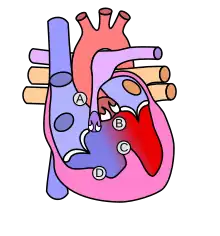

![]() | |

| Diagram of a healthy heart and one with tetralogy of Fallot | |

Four malformations

"Tetralogy" denotes four parts, here implying the syndrome's four anatomic defects.[2] This is not to be confused with the similarly named teratology, a field of medicine concerned with abnormal development and congenital malformations (including tetralogy of Fallot). Below are the four heart malformations that present together in tetralogy of Fallot:

| Pulmonary Infundibular Stenosis | A narrowing of the right ventricular outflow tract. It can occur at the pulmonary valve (valvular stenosis) or just below the pulmonary valve (infundibular stenosis).[4] Infundibular pulmonic stenosis is mostly caused by the overgrowth of the heart muscle wall (hypertrophy of the septoparietal trabeculae),[41] however, the events leading to the formation of the overriding aorta are also believed to be a cause. The pulmonic stenosis is the major cause of the malformations, with the other associated malformations acting as compensatory mechanisms to the pulmonic stenosis.[42] The degree of stenosis varies between individuals with TOF and is the primary determinant of symptoms and severity. This malformation is infrequently described as sub-pulmonary stenosis or subpulmonary obstruction.[43] |

| Overriding aorta | An aortic valve with biventricular connection, that is, it is situated above the ventricular septal defect and connected to both the right and the left ventricle. The degree to which the aorta is attached to the right ventricle is referred to as its degree of "override." The aortic root can be displaced toward the front (anteriorly) or directly above the septal defect, but it is always abnormally located to the right of the root of the pulmonary artery. The degree of override is extremely variable, with 5-95% of the valve being connected to the right ventricle.[41] |

| Ventricular septal defect (VSD) | A hole between the two bottom chambers (ventricles) of the heart. The defect is centered around the most superior aspect of the ventricular septum (the outlet septum), and in the majority of cases is single and large. In some cases, thickening of the septum (septal hypertrophy) can narrow the margins of the defect.[41] |

| Right ventricular hypertrophy | The right ventricle is more muscular than normal, causing a characteristic boot-shaped (coeur-en-sabot) appearance as seen by chest X-ray. Due to the misarrangement of the external ventricular septum, the right ventricular wall increases in size to deal with the increased obstruction to the right outflow tract. This feature is now generally agreed to be a secondary anomaly, as the level of hypertrophy tends to increase with age.[44] |